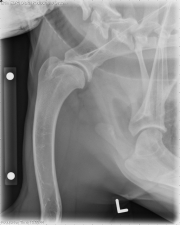

Today’s case is a 2-year-old female neutered German  Shepherd mix with a 5-week history of intermittent left thoracic limb lameness that worsens with exercise. Take a look and post your interpretation!

Left shoulder: On the lateral radiograph, there is flattening of the caudal aspect of the humeral head with a linear mineral density that is separated from the joint surface. There is mild sclerosis of the caudal humeral head. Osteophytes are present on the caudal glenoid as well as in the inter-turburcular groove. On the ventrodorsal projections, osteophytes are additionally visible on the medial and lateral aspects of the glenoid.

Right shoulder: On the lateral radiograph, the caudal humeral head is flattened and irregular with mild sclerosis of the subchondral bone. There are small osteophytes present on the caudal and distal glenoid as well as the inter-turburcular groove.

Bilateral shoulder osteochondrosis. Arthroscopy was performed and confirmed the radiographic findings, with left bicipital tendonitis.